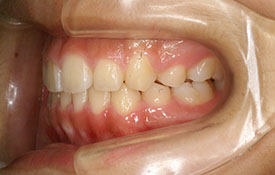

上顎前突|ブラケットを用いた治療

CASE 1

CASE 2